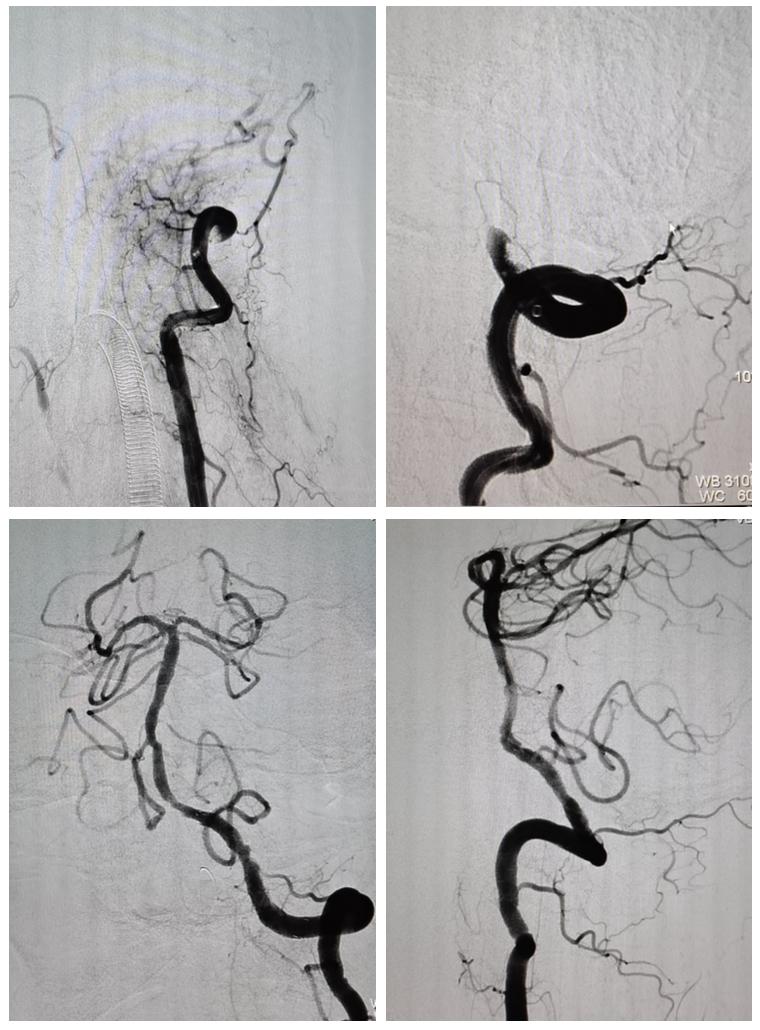

患者因头晕伴走路偏斜收入我科,入院时言语流利,四肢活动自如,可独立行走,完善相关检查证实为后循环梗死。住院期间,患者突然症状加重,突发右侧肢体完全瘫痪,肌力0级,伴头晕加重、言语含糊,眼球活动受限。刘大成住院总医师研判后考虑梗死症状加重,立即启动“卒中绿色通道”,一切检查优先安排,迅速完成头CT及一站式多模式MR检查,结果提示后循环脑梗死病灶明显扩大,基底动脉未显影。神经内科副主任张茹教授当即指示,患者后循环梗死,病情进展,基底动脉未显影,如不及时处理,症状仍有可能进一步恶化,病情极其凶险,应立即行脑血管造影评估手术指证。由范清雨主治医师、张磊医师、张倩护士及蒋鹏鹏护士组成的介入团队迅速到岗,正值神经内科王虎清教授担任当天全院总值班,王虎清教授亲自到场上台主刀手术。患者造影结果提示左侧椎动脉V4段闭塞,介入团队综合研判为此病情进展责任血管,具有行急诊取栓手术指征,充分向患者家属告知病情并征得同意后实施手术,最终成功再通闭塞血管,基底动脉显影良好(图1)。患者术后右侧肢体力量明显好转,肌力IV级,可自主上抬(图2)。目前患者仍在积极康复治疗中。

图1 上图:取栓术前血管闭塞; 下图:取栓术后血管成功再通